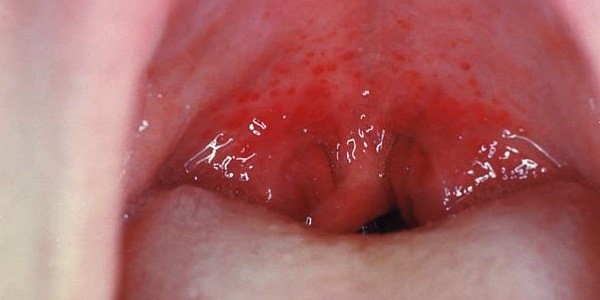

Герпетическая ангина

Это крайне заразное инфекционное заболевание. Его главный симптом – появляются на задней стенке горла волдыри с прозрачным содержимым. Они называются везикулами и образуются в большом количестве.

Важно. Светлые узелки ярко выделяются на фоне ярко-красных слизистых горла. Удалять их самостоятельно нельзя. поскольку на их месте могут образоваться болезненные язвочки.

Волдыри на задней стенке горла: фото-материалы ниже.